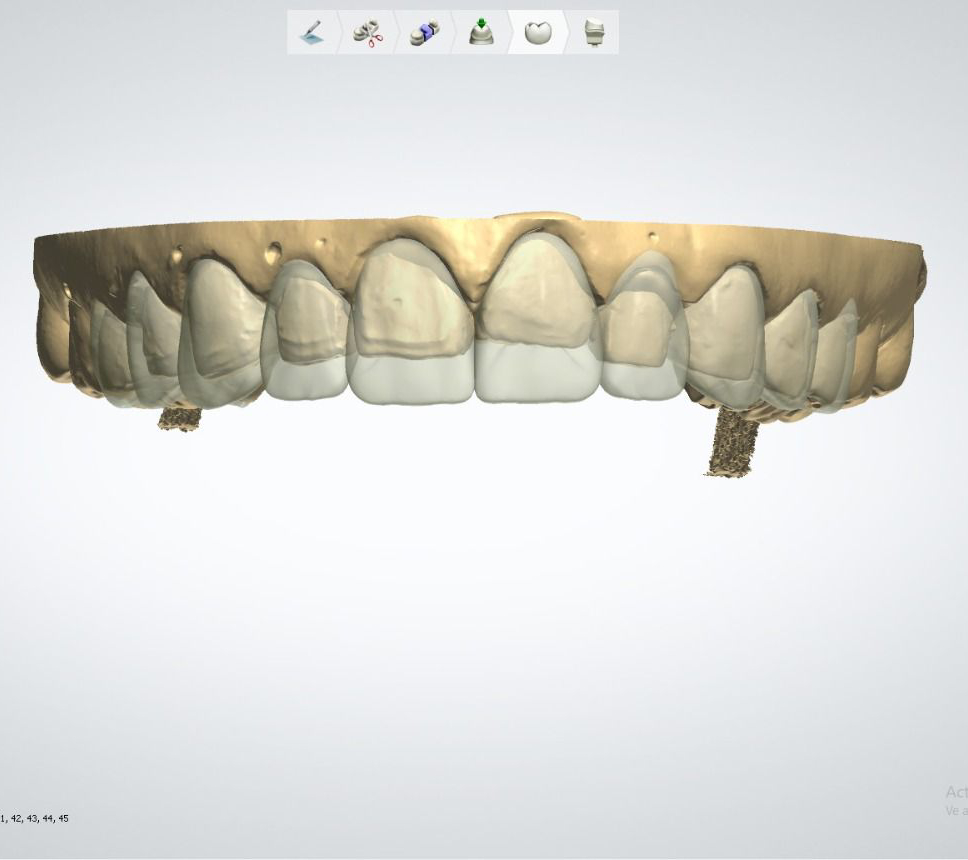

Casos de éxito

Estos son algunos de nuestros casos de éxito, mostrando el antes y después de nuestras intervenciones.

Rehabilitación de la arcada superior con zirconia monolítico multicapa.

Rehabilitación superior e inferior con zirconia monolítico multicapa en color B1.

Diseño de carillas de premolar a premolar, tanto superior como inferior.